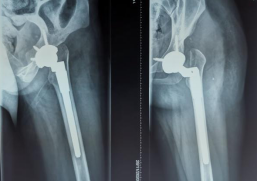

通过小张的骨盆X线可以看到,她的左侧髋臼是一个发育不良的状态,髋臼较小较浅,外展角较大,而股骨头已经完全脱位,根据脱位高度分型为DDH(developmental dysplasia hip,发育性髋关节发育不良)IV型,已经属于最严重的程度了。

(下肢不等长,Allis征+) (骨盆正位片)

(术后X线)